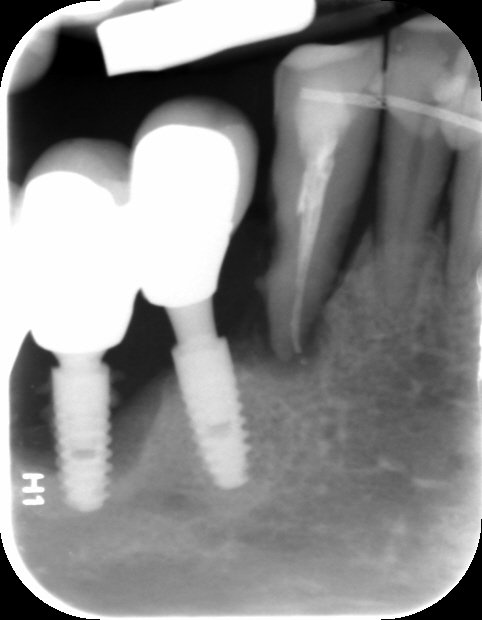

primer y tercer implante no se que marca son

EL paciente ha venido con el primer y tercer implante que se ve en la periapical y no se cuales son? conocéis esa marca de implantes? gracias.